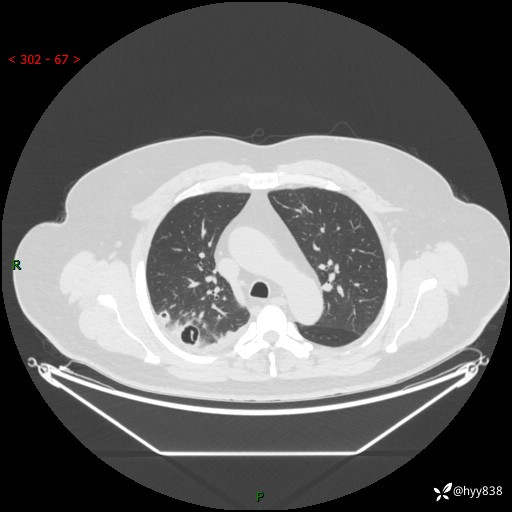

性别:男

年龄:48岁

简要病史:发热来诊(门诊病人)

胸部CT平扫